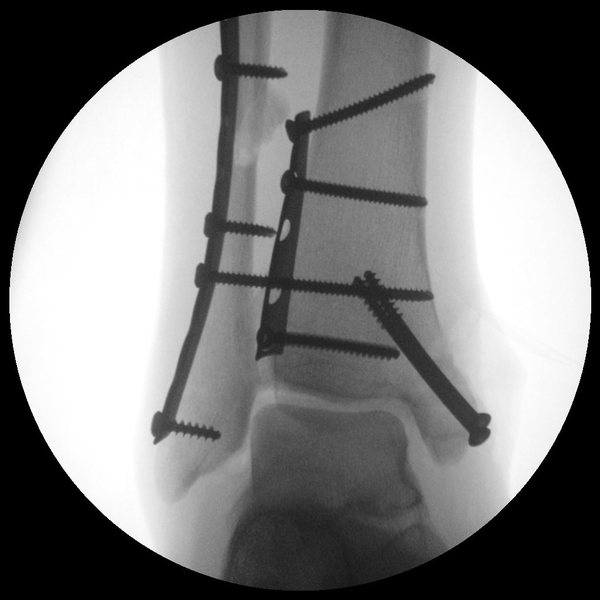

Removing Hardware From Ankle . In these cases, the hardware may not be entirely removed or larger incisions will be made. Elevate the leg as much as possible, above heart level. Many foot and ankle procedures require insertion of metal plates, screws, rods, or similar implants for stabilization of the bones while they heal. Some or all of the hardware may be removed. Because people have little fat or muscle over the bones around the ankle, many people can feel the screws there with sports and exercise. It does take time to recover from the second. Every injury is different and everyone heals at different rates. Use ice as much as possible. Speak with your healthcare provider to find out what you. This can be done in the office or with mild sedation (twilight sleep) in. Rom and strength gains can usually be made quickly, and within 4 to 6 weeks you should nearer to your preoperative level of function. After most surgeries, the hardware causes little trouble to the patient. You can expect to start physical therapy a few weeks after your hardware removal surgery. If you do have discomfort, removing the screws or plate and screws can relieve that pain. Some of it may not reach the.

External fixators (pins and bars outside the skin) are routinely removed. Use ice as much as possible. In these cases, the hardware may not be entirely removed or larger incisions will be made. Speak with your healthcare provider to find out what you. Sometimes, screws may break or be very hard to find. If you do have discomfort, removing the screws or plate and screws can relieve that pain. Some or all of the hardware may be removed. Every injury is different and everyone heals at different rates. Place over the top of the foot. Because people have little fat or muscle over the bones around the ankle, many people can feel the screws there with sports and exercise.

Removing Hardware From Ankle Some of it may not reach the. You can expect to start physical therapy a few weeks after your hardware removal surgery. Many foot and ankle procedures require insertion of metal plates, screws, rods, or similar implants for stabilization of the bones while they heal. Sometimes, screws may break or be very hard to find. At least three to six months have passed since the original. Place over the top of the foot. Elevate the leg as much as possible, above heart level. No matter what or how severe your injury is, a good time to take our hardware is when: It does take time to recover from the second. After most surgeries, the hardware causes little trouble to the patient. Rom and strength gains can usually be made quickly, and within 4 to 6 weeks you should nearer to your preoperative level of function. Every injury is different and everyone heals at different rates. In these cases, the hardware may not be entirely removed or larger incisions will be made. This can be done in the office or with mild sedation (twilight sleep) in. If you do have discomfort, removing the screws or plate and screws can relieve that pain. External fixators (pins and bars outside the skin) are routinely removed.